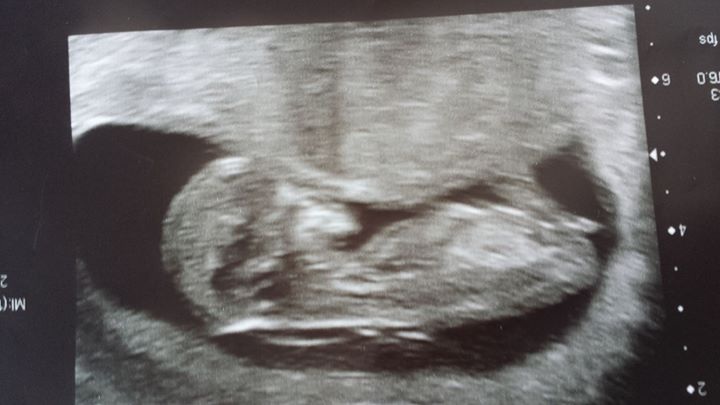

Hi, had my scan on Friday at 12+2, I don't know whether what I'm looking at is a nub or just the cord or something? Anyone know, and want to hazard a guess at the gender? Thanks

Thinking maybe girl, congrats!

If that's the nub thinking girl

Girl. Congrats on baby x